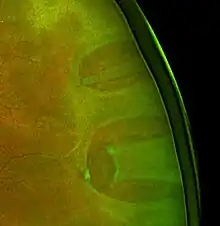

Tear related retinal detachment – the retina has a horseshoe-shaped defect.